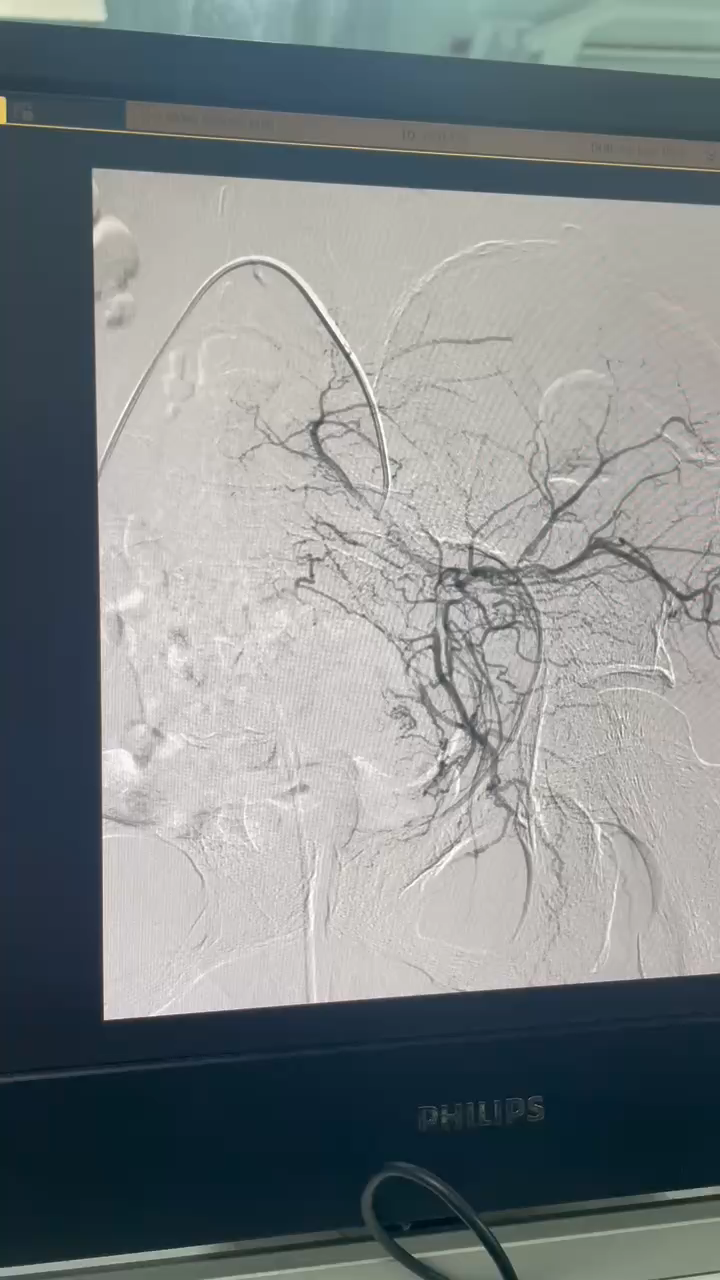

肾挫裂伤治疗~超选择肾动脉栓塞术

病例信息【患者信息】:女性,56岁【主诉】:摔伤至全身多处疼痛1小时【现病史及既往史】:1小时前患者骑车回家时不慎侧滑摔倒,伤后患者出现全身多处疼痛,左侧腰腹部较明显,呈持续钝痛,疼痛可忍受,伤时无昏迷,伤后能回忆受伤经过,伴偶尔咳嗽,无明显咳痰,咳嗽时左侧腰腹部疼痛较明显,后由路人拨打120,由120送入我院急诊科,完善相关检查提示“左肾挫裂伤、左侧气胸”,经请我科会诊后以“左肾挫裂伤”收治入院。 既往5年前因“右肾多发结石并右肾重度积水、右侧输尿管上段狭窄”行“右侧经皮肾镜碎石取石术+右侧输尿管支架置入术”。【检查】:颅脑CT平扫、胸部CT平扫、上腹部CT平扫、下腹部CT平扫、颈椎CT平扫